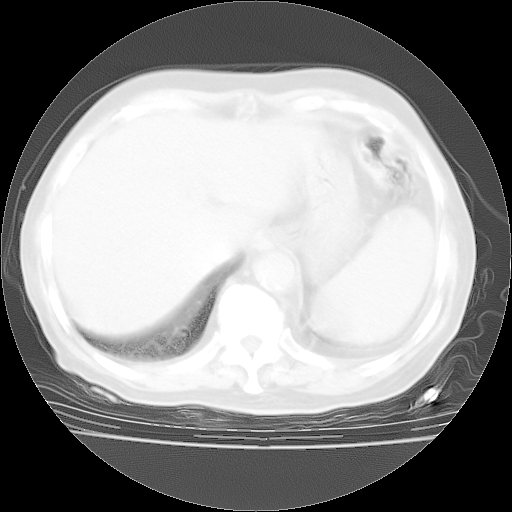

4月28日肺部CT——再次出现类似去年5月9日——透光度降低,“间质性”改变。

4月28日肺部CT——再次出现类似去年5月9日——磨玻璃样、间有“粟粒样”改变。